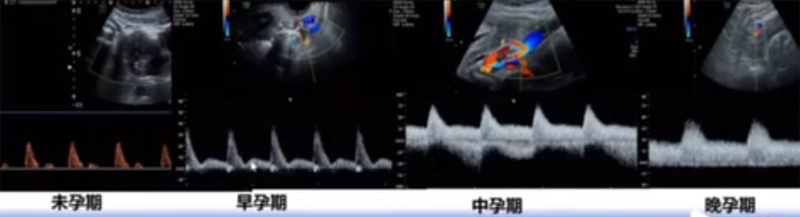

位于输卵管的后下方,子宫两侧的后上方;借卵巢系膜与子宫阔韧带后层相连。正常成人卵巢约4x3x2cm,跟睾丸的数值差不多,都是性器官,绝经后卵巢萎缩变小、变硬。所以绝经后妇女很难找到卵巢,主要功能:生殖和内分泌功能分泌性激素。女性的第二性征。女性内生殖器的血管分布,动脉有子宫动脉,卵巢动脉,阴道动脉,阴部内动脉。静脉它是与动脉伴行。重要了解的是子宫动脉,子宫动脉是髂内动脉前干的重要分支,妊娠时候血流速度会增加的,为无创性检查胎盘血管阻力的方法。未孕期频谱为高阻力低舒张波形;正常妊娠时血流速度增加,血流阻力下降。